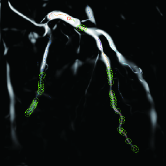

Figure 6: Overall experimental results of our proposed solution. (a) Original images. (b) Vessel contour extraction after image preprocessing. (c) Vessel segmenting. (d) Automatic stenosis detection. (e) Interactive stenosis detection

To make a preliminary test on the effectiveness of our proposed solution, we selected three images with large differences in vessel structures for independent experiments and the results are shown in Fig. 6. As can be seen from the figures, even though the vessel structures are different, the whole algorithm in this paper still has a good experimental effect on each image. Next, we will give more detailed and quantitative results of our methods.